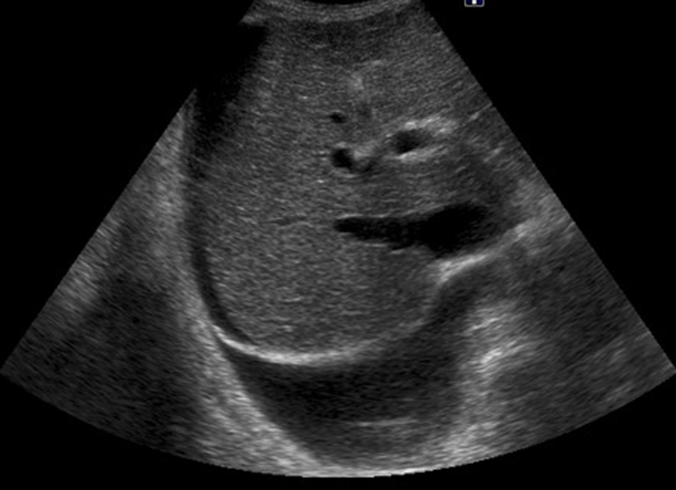

Se realiza ecoscopia no reglada, con imagen compatible con ascitis.

Ante los hallazgos se deriva a urgencias hospitalaria, allí confirman liquido libre en espacio de Morrison, en dicho líquido se observan imágenes redondeadas, móviles de contenido heterogéneo e hiperecogénicas y formación anexial solido – quística.

Con este caso se muestra cómo un cuadro inicialmente compatible con infección urinaria puede ocultar una patología oncológica avanzada, destacando el valor de la ecografía clínica en Atención Primaria para identificar signos de alarma como ascitis.